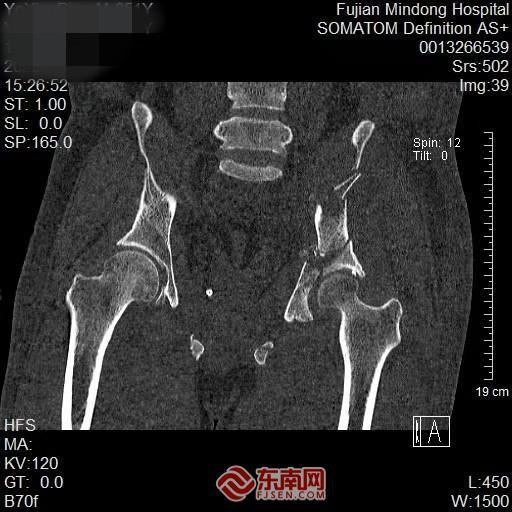

患者叶先生因驾车自高处坠落导致髋部剧痛,经急诊CT检查确诊为“左侧髋臼粉碎性骨折”。髋臼作为髋关节的核心结构,其骨折手术难度大、风险高,被誉为创伤骨科领域的“金字塔尖”手术。传统手术面临解剖结构复杂、重要血管神经密集、复位精度要求高、固定难度大等挑战。

为攻克这一难题,医疗团队迅速启动3D打印辅助精准手术预案。通过采集患者1毫米薄层CT数据,成功打印出与骨折部位1:1等大的高保真髋臼模型。该模型将二维影像转化为可触可感的实体,使骨折类型、骨块移位距离、关节面破坏程度一目了然。

术前影像。闽东医院供图